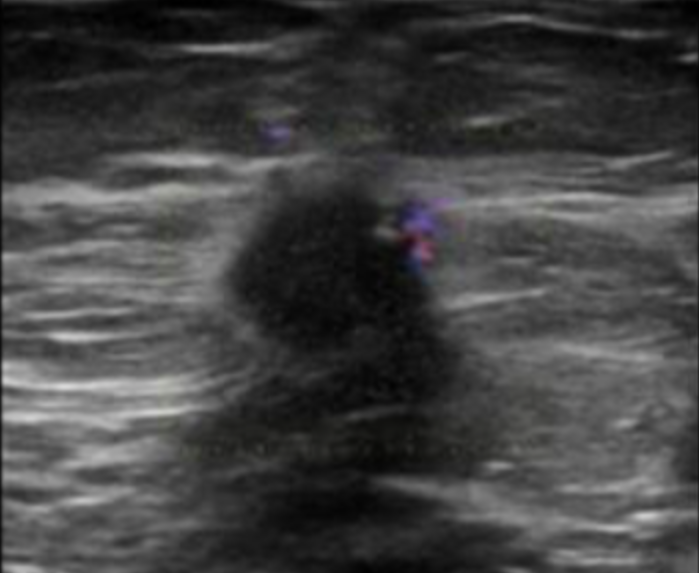

<p>What type of transducer produced the image?</p><p>a. sector phased array <br>b. linear sequential array <br>c. curved sequential array <br>d. vector phased array</p>

What type of transducer produced the image?

a. sector phased array

b. linear sequential array

c. curved sequential array

d. vector phased array

vector phased array